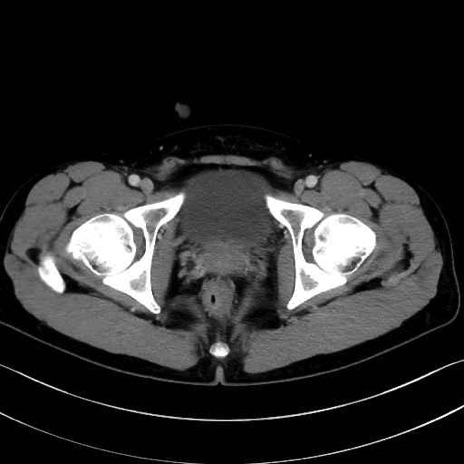

大腿方形筋(Quadratus femoris muscle)のCT画像の解剖

4. 深層外旋六筋(股関節の深部)

梨状筋 (Piriformis)

内閉鎖筋 (Obturator internus)

外閉鎖筋 (Obturator externus)

大腿方形筋 (Quadratus femoris)